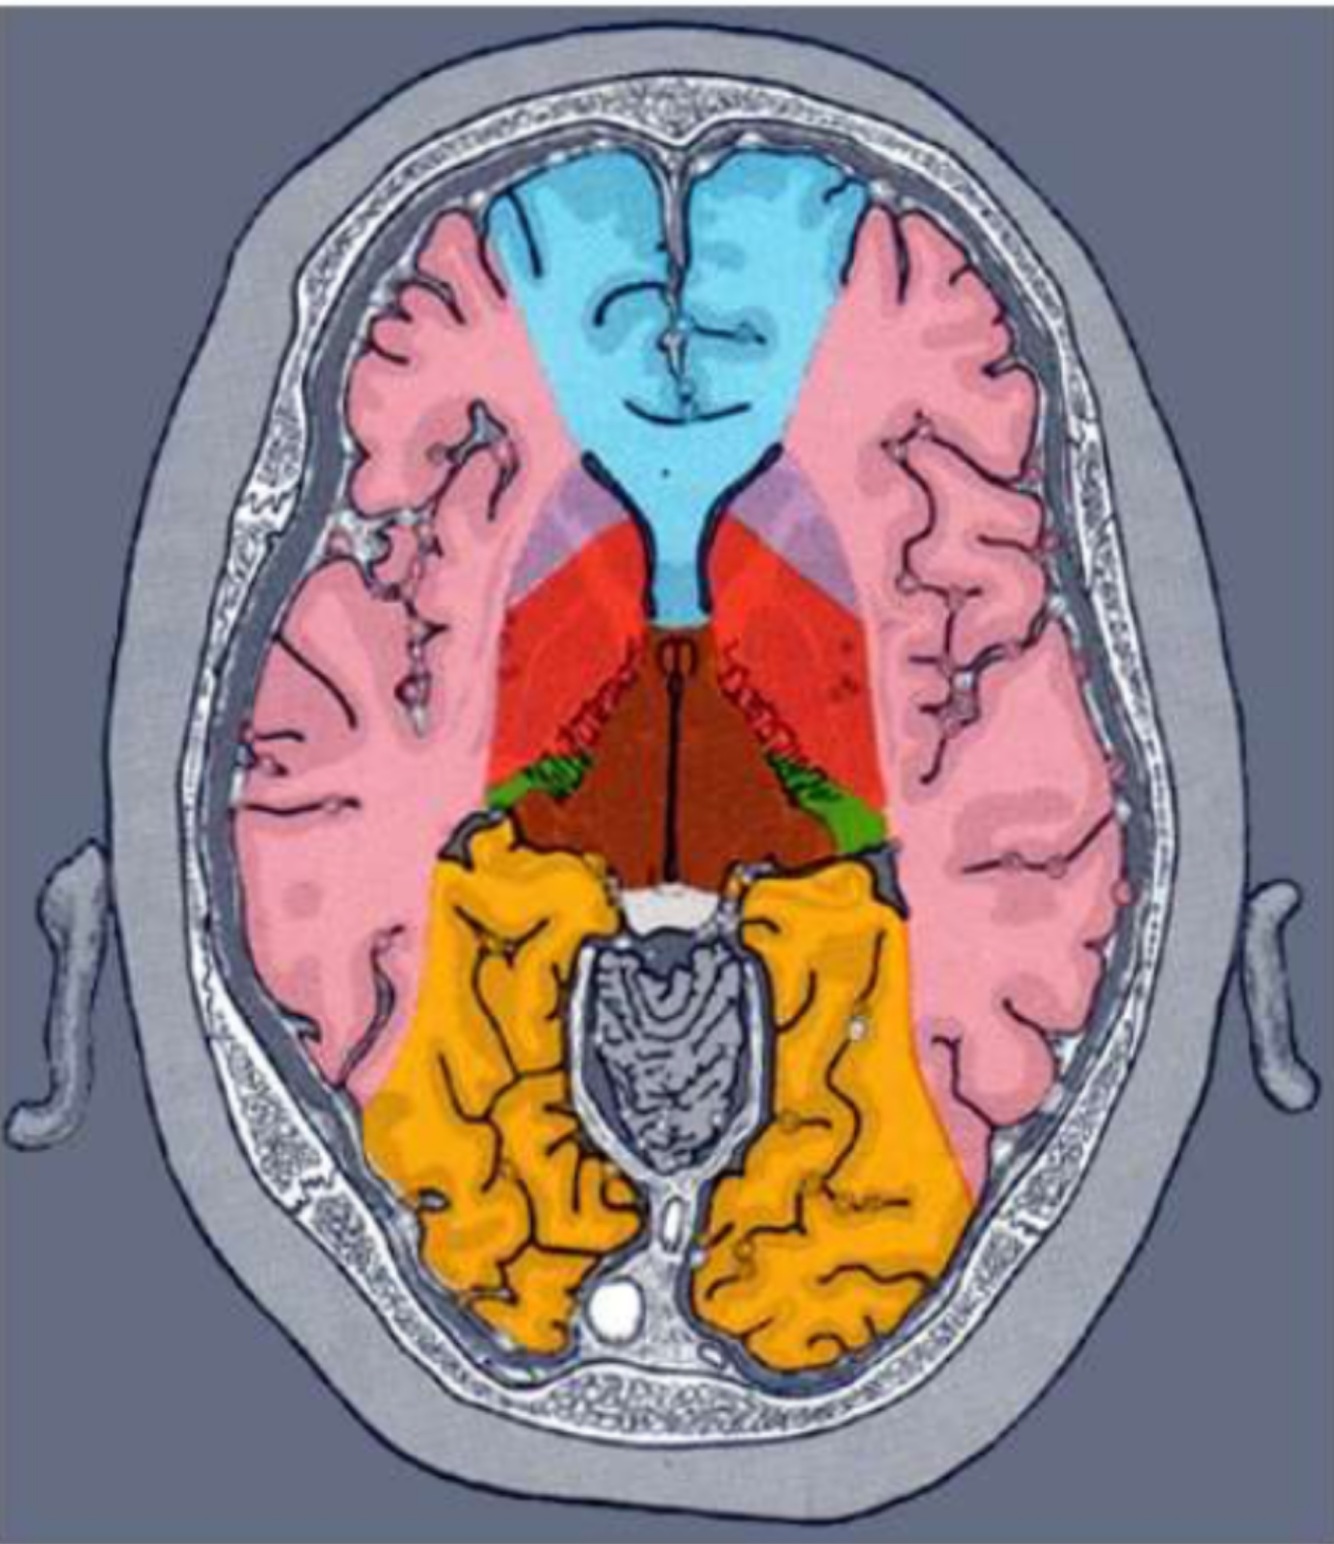

Q

Menciona las arterias

A